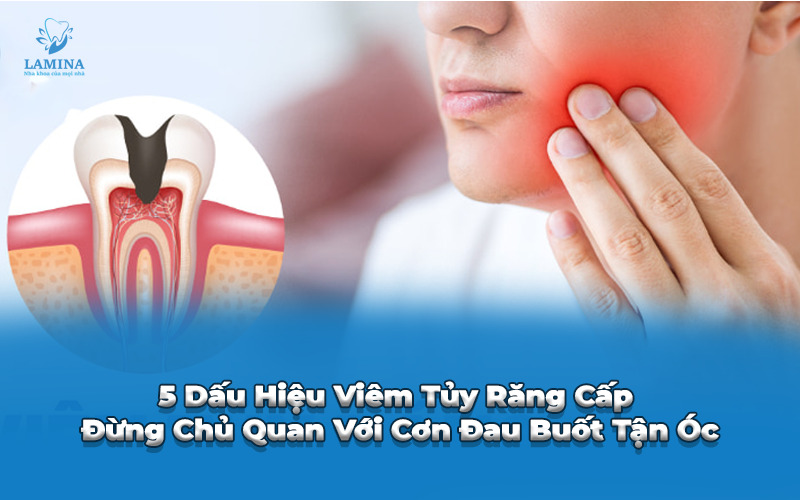

5 Dấu Hiệu Viêm Tủy Răng Cấp Đừng Chủ Quan Với Cơn Đau Buốt Tận Óc

Trong các bệnh lý về răng miệng, viêm tủy răng cấp tính được ví như một “cơn ác mộng” bởi những cơn đau dữ dội, xuất hiện bất thình lình và gây ảnh hưởng nghiêm trọng đến sức khỏe, tâm lý người bệnh. Nếu không nhận biết sớm các dấu hiệu viêm tủy răng cấp, vi khuẩn sẽ nhanh chóng phá hủy toàn bộ cấu trúc răng, dẫn đến áp xe hoặc mất răng hoàn toàn.

1. Viêm tủy răng cấp là gì?

Tủy răng là một tổ chức liên kết đặc biệt gồm mạch máu và dây thần kinh, nằm trong buồng tủy và ống tủy, được bao bọc bởi men răng và ngà răng. Viêm tủy răng cấp là tình trạng viêm nhiễm bùng phát mạnh mẽ ở tổ chức tủy trong thời gian ngắn.

Khác với viêm tủy mãn tính diễn tiến âm thầm, các dấu hiệu viêm tủy răng cấp thường diễn ra dồn dập, cường độ đau cao và khiến người bệnh không thể tập trung làm việc hay nghỉ ngơi. Đây là giai đoạn “báo động đỏ” cần sự can thiệp ngay lập tức của bác sĩ nha khoa.